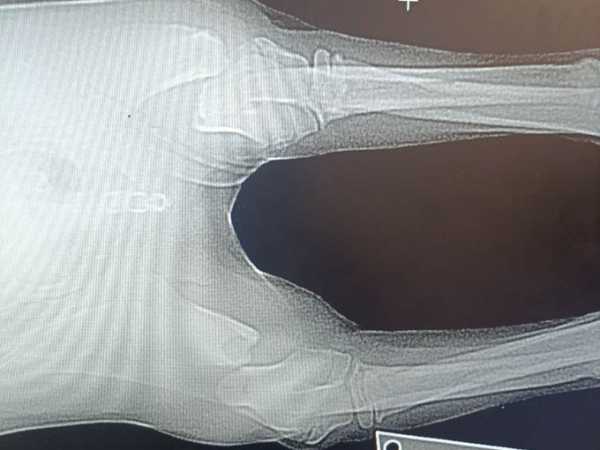

Приблизительно 19 сентября этого беднягу нашли. Он лежал неподвижно, у него были жуткие переломы передних лап. Волонтеры думают, что его просто выкинули из машины на скорости, судя по характеру повреждений.

– Только так мы можем объяснить такие дикие и параллельные переломы на обеих передних лапках, – рассказывает Ольга.